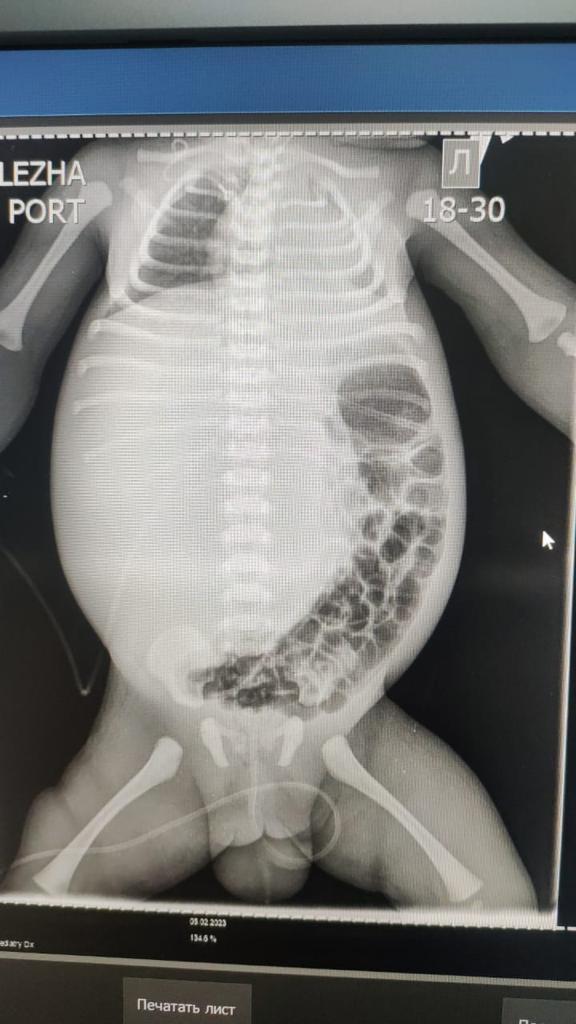

Гигантская опухоль печени занимала всю правую долю печени и была обнаружена сразу после рождения ребенка. 3 февраля трехдневный ребенок был переведен в Научный центр педиатрии и детской хирургии.

В течение пяти дней проводилась коррекция состояния и консервативное лечение. За короткое время объем живота увеличился с 38 см до 44 см. Образование сдавливало внутренние органы, в связи с чем ребенок находился на аппарате ИВЛ. Учитывая эти обстоятельства, мультидисциплинарно было решено провести оперативное лечение в срочном порядке.

№1 - Ангиография. Рентгенэндоваскулярная эмболизация правой печеночной артерии.

№2 – Лапаротомия, правосторонняя гемигепатэктомия. Дренирование брюшной полости. Такая комбинированная операция никогда не проводилась в нашей стране.